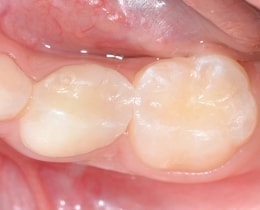

④治療後

虫歯を全て取り除き、コンポジットレジンと呼ばれる白い材料で詰めました。

※1回で治療終了です。